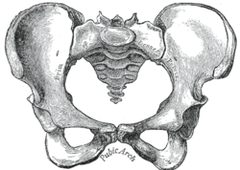

産後の骨盤矯正はとても重要です。 なぜ重要なのか、知っている方は少ないと思います。 お子さんを産んでから腰痛、肩こり、股関節痛や産後太りになってしまい、お悩みになる女性がとても多いのです。 そうならないためにも、産後の骨盤矯正が大切なことを説明したいと思います。 女性の骨盤(下左図)は男性(下右図)に比べ幅が広い形で骨盤が大きく、開いています。